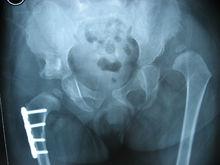

3. 18月齡到8歲患兒

大於18月齡的DDH患兒髖臼發育潛力很差,在做髖關節切開復位的同時多數需要做骨盆截骨術,4歲內的DDH患兒可以選擇Salter、Pemberton、Dega等骨盆截骨,對於脫位高、復位後關節壓力大、前傾角和頸乾角大的患兒需要同時做股骨近端的短縮、去鏇轉和內翻截骨。對於大於4歲的患兒在做上述手術同時,對於手術後再次脫位等複雜情況,也可以進行骨盆三聯截骨手術。具體手術方式的選擇,醫生需要根據髖關節的病理改變、患兒年齡等因素來決定。

發育性髖關節發育不良雙側髖關節脫位

發育性髖關節發育不良右髖切開復位、Pemberton骨盆截骨、股骨近端短縮去鏇轉截骨術後

發育性髖關節發育不良右側術後8個月